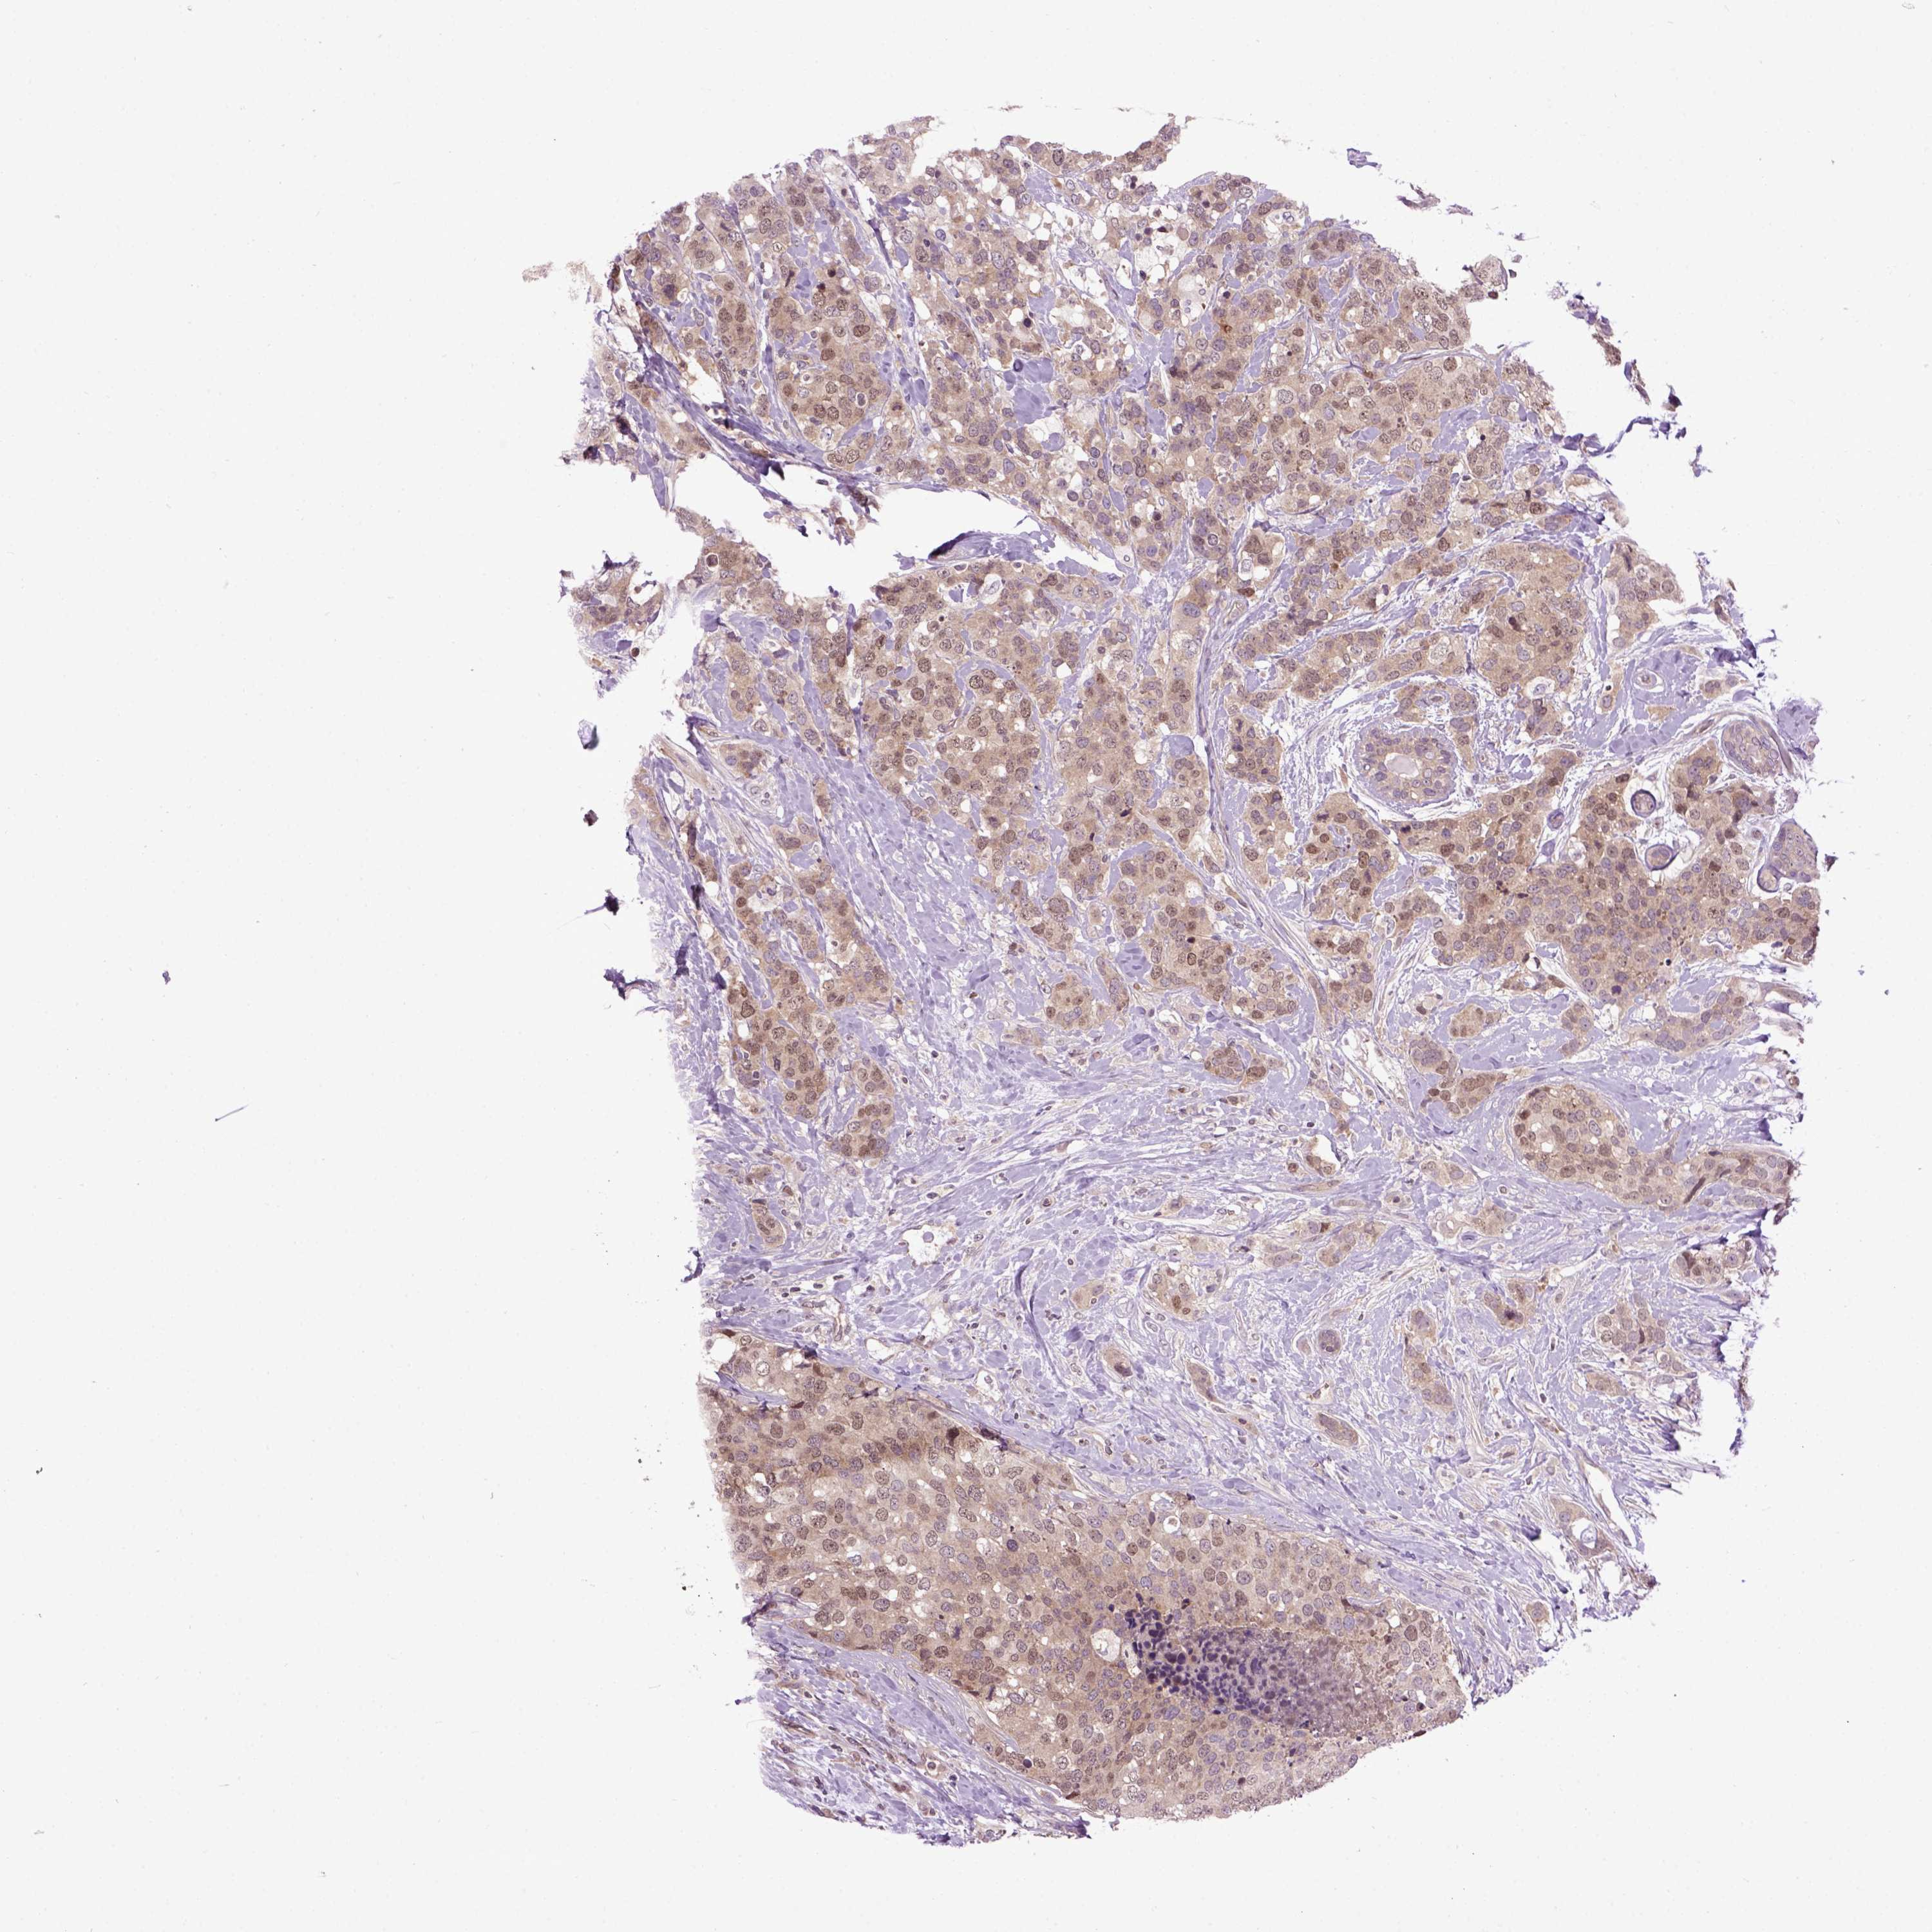

CANCER BREAST CANCER Show tissue menu

BRCA TCGA BRCA VALIDATION PROTEIN EXPRESSION